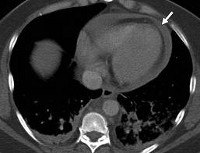

Диагноз гемоперикарда устанавливается кардиохирургом на основании характерных клинических проявлений, изучения возможных причин заболевания, данных рентгенографии грудной клетки, электрокардиографии (ЭКГ), эхокардиографии (ЭхоКГ), перикардиоцентеза.

Для электрокардиограммы при гемоперикарде характерно снижение вольтажа желудочковых комплексов, наличие изменений, отражающих основную патологию сердца (инфаркт миокарда). При эхокардиографии разрыв эхосигналов между стенками сердца и перикардом позволяет обнаружить наличие даже небольшого по размерам гемоперикарда.

Подтверждением диагноза гемоперикарда при рентгенографии органов грудной клетки является увеличение тени сердца во всех направлениях, сглаженность сердечных дуг, уменьшение амплитуды или отсутствие пульсации контуров. При удовлетворительном состоянии больного с гемоперикардом выполняют динамическое рентгенологическое исследование, позволяющее установить скорость накопления крови в перикарде по нарастанию тени сердца.